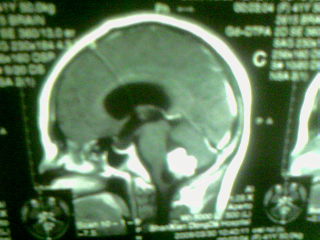

标题: MRI2125:女 45岁 头疼头晕3个月 [打印本页]

标题: MRI2125:女 45岁 头疼头晕3个月

1)考虑第四脑室脉络膜丛乳头状瘤,不排除室管膜瘤。2)阻塞性脑积水。

考虑 第四脑室室管膜瘤或脉络膜丛乳头状瘤伴梗阻性脑积水。

1)考虑第四脑室室管膜瘤,不排除脉络膜丛乳头状瘤。2)阻塞性脑积水。

考虑 第四脑室脑膜瘤或室管膜瘤或脉络膜丛乳头状瘤伴梗阻性脑积水

第四脑室脉络丛乳头状瘤,典型!